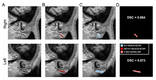

연세대학교 용인세브란스병원(병원장 김은경) 이비인후과 김주현최은창 교수 연구팀은 볼 중앙 및 이하선(귀밑샘) 전방 종양 제거를 위해 시행한 로봇 수술이 전통적인 개방 수술과 비…